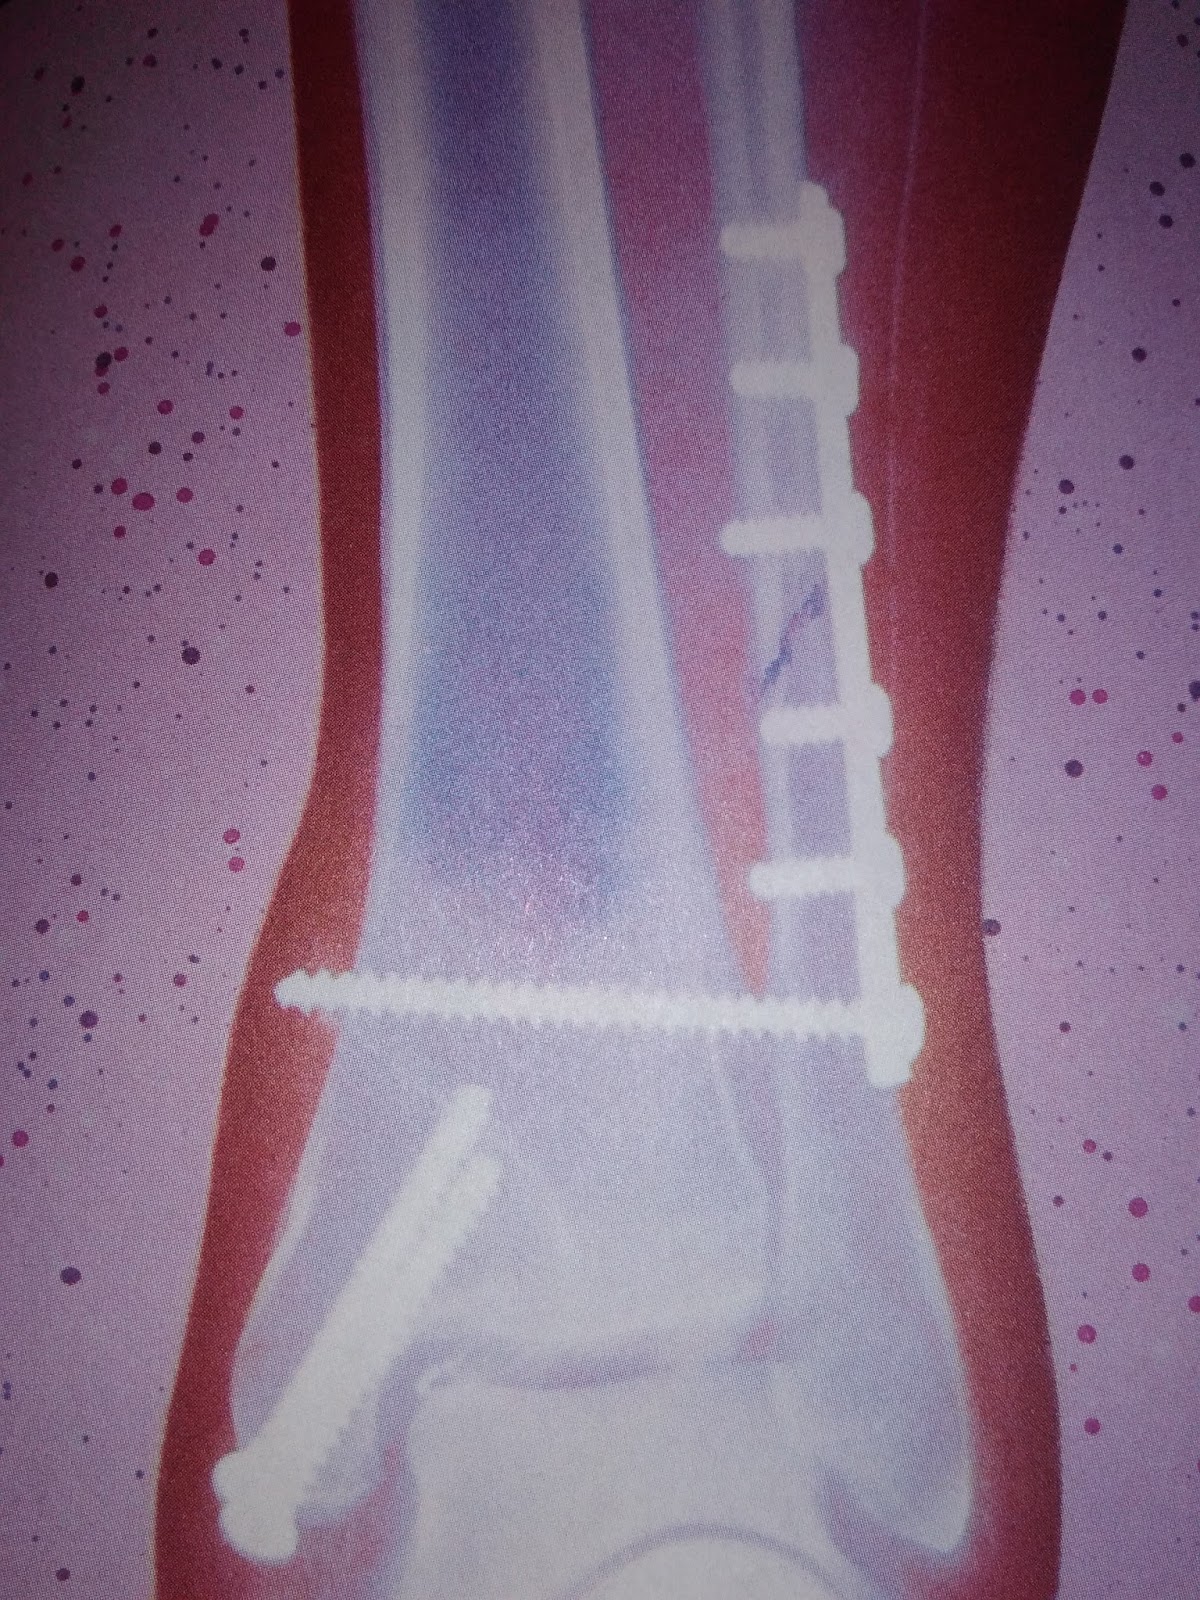

Contoh foto x-ray dengan pen di dalam.

Saat dirontgen atau di x-ray pun timbul lagi pertanyaan Duo Lynns. Kenapa tulang dapat terlihat saat di x-ray.  Lalu kenapa adik tidak boleh masuk untuk melihat. Maklum, Duo Lynns tidak takut dengan namanya dokter. Jadi saat dilarang masuk, adik malah galau. Dari buku ini juga kami menemukan jawaban dari pertanyaan kakak. Bagaimana cara kerja mesin x-ray? Mesin x-ray menembakkan elektron-elektronnya melalui tubuh kita. X-ray bergerak melalui daging tetapi sinar tersebut terhenti saat bertemu dengan tulang. Bagian tulang akan terlihat dengan warna putih dan bagian yang lain dengan warna hitam. Pada bagian yang retak, pada hasil rontgen akan muncul warna hitam yang membentuk garis tipis di tengah-tengah tulang yang putih. Karena radiasi dari elektron-elektron yang ada, maka adik tidak diizinkan masuk. Jawaban ini lumayan mendiamkan adik dan membuat adik mempunyai konklusi lain untuk meminta papa mencari film tentang mesin x-ray

Contoh mesin x-ray